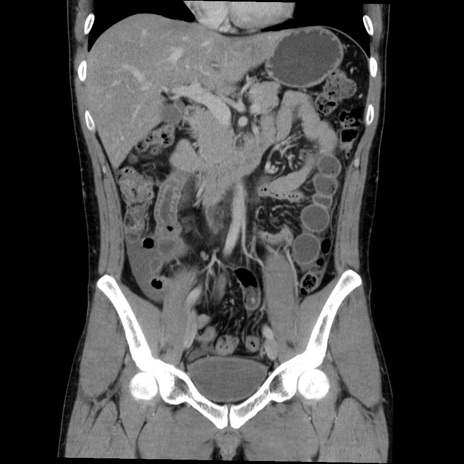

症例36(冠状断像)

【症例】20歳代 男性

【主訴】心窩部痛

【現病歴】今朝より上腹部痛あり。一旦軽快していたが再度出現したため救急要請。昨日夕に白身の魚を含む刺身を食べた。

【身体所見】BP 136/89mmHg、HR 74/min、BT 37.0℃、腹部:膨満、軟、心窩部に圧痛あり。反跳痛なし、筋性防御なし、腸雑音やや亢進あり。

【データ】WBC 17700、CRP 0.48